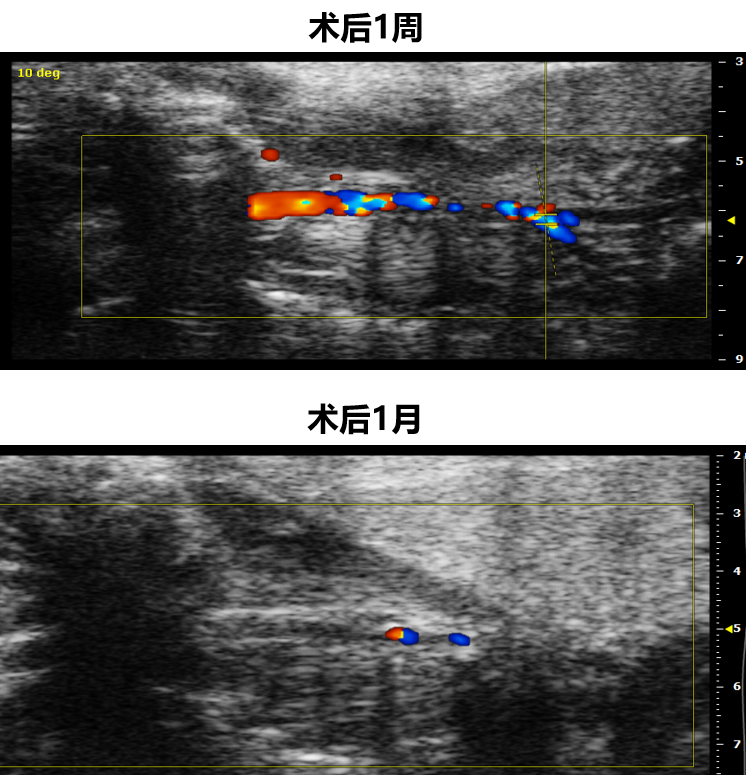

研究团队成功建立了慢性颈动脉闭塞(CCAO)小鼠模型。

难点: 需要区分急性和慢性过程,避免急性血栓导致的大面积脑梗死(这会直接致死或造成明显神经功能缺损)。

结果: 术后1周表现为狭窄,术后1个月实现完全闭塞,且小鼠未出现急性卒中表现,模拟了人类的“无症状”慢性病程。

图:小鼠CCAO模型建立